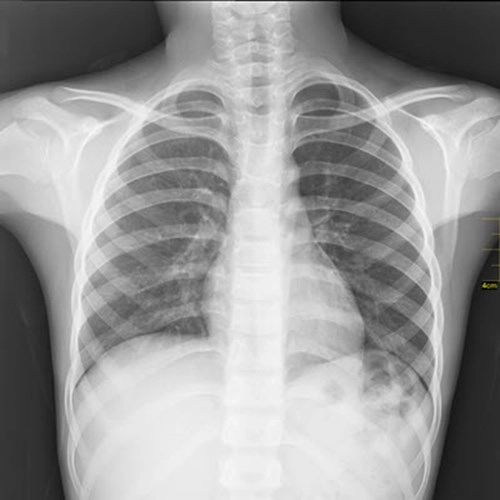

Statistics at school might seem pretty text-book heavy, but in the real world there are so many exciting ways you might use it on the job. Just as important as a stethoscope to a next-gen doctor’s kit are skills in collecting, analysing and drawing conclusions from quantitative data. This niche skillset not only helps with diagnosing and treating patients, but also in communicating with them about their conditions too.

Nurses, for instance, use statistics to identify patterns in symptoms and determine whether a patient needs immediate medical attention or follow-up care.